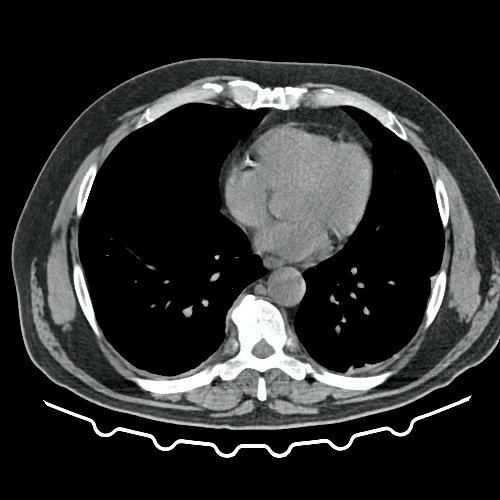

• TAC de tórax con contraste EV (Día 10): La porción visualizada de la glándula tiroides es de características normales. Las estructuras vasculares supraaórticas son de características normales, permeables. La aorta ascendente, el cayado y la aorta descendente son de calibre y trayecto conservados, permeables. Las estructuras venosas mediastinales: vena cava superior, vena cava inferior, venas pulmonares superiores e inferiores y venas ácigo-hemiácigos, son de calibre y trayecto conservado, permeables. Vena ácigos prominente. La arteria pulmonar y sus ramas son de calibre y trayecto conservados, permeables. Relación aórtico-pulmonar conservada. El corazón es de tamaño normal. El pericardio es de espesor conservado. El esófago es de calibre y trayecto normales. El mediastino está en posición central. No se observan adenomegalias mediastinales, axilares o hiliares. El árbol traqueobronquial no presenta alteraciones. Aisladas atelectasias laminares en ambos lóbulos inferiores y en segmento lingular inferior. No se observa engrosamiento o derrame pleural. Marcados cambios osteoartrósicos de la columna dorsal.

TAC de tórax, abdomen y pelvis con contraste EV (Día 10) Corte axial